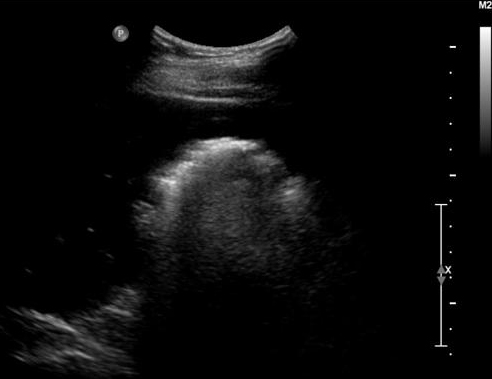

Epaissisement de la

paroi vesiculaire > 3mm , la contenue est irregulie

et image de calcul de infundibulum vesiculaire

. Cholecystite aigue lithiasique |